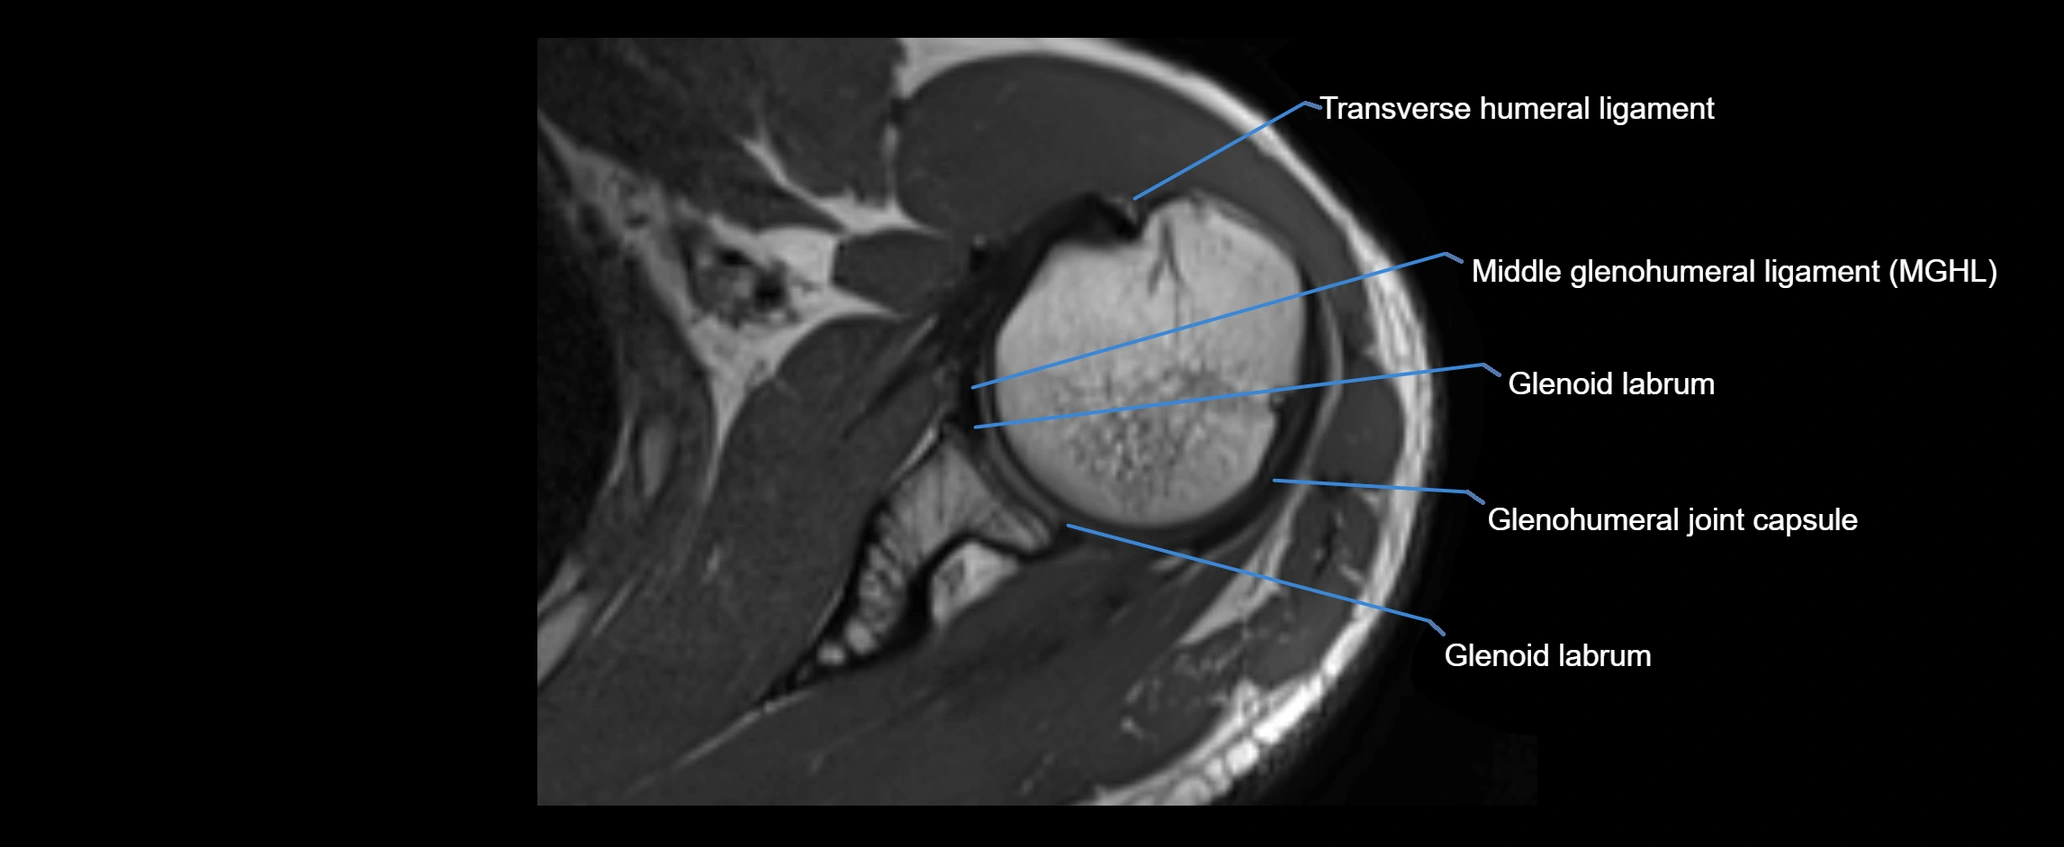

CT image

image

MRI Appearance

• T2-weighted images:

• Proton Density Fat-Saturated (PD FS):

• Excellent for assessing joint capsule, coracoclavicular ligaments, and periarticular edema.